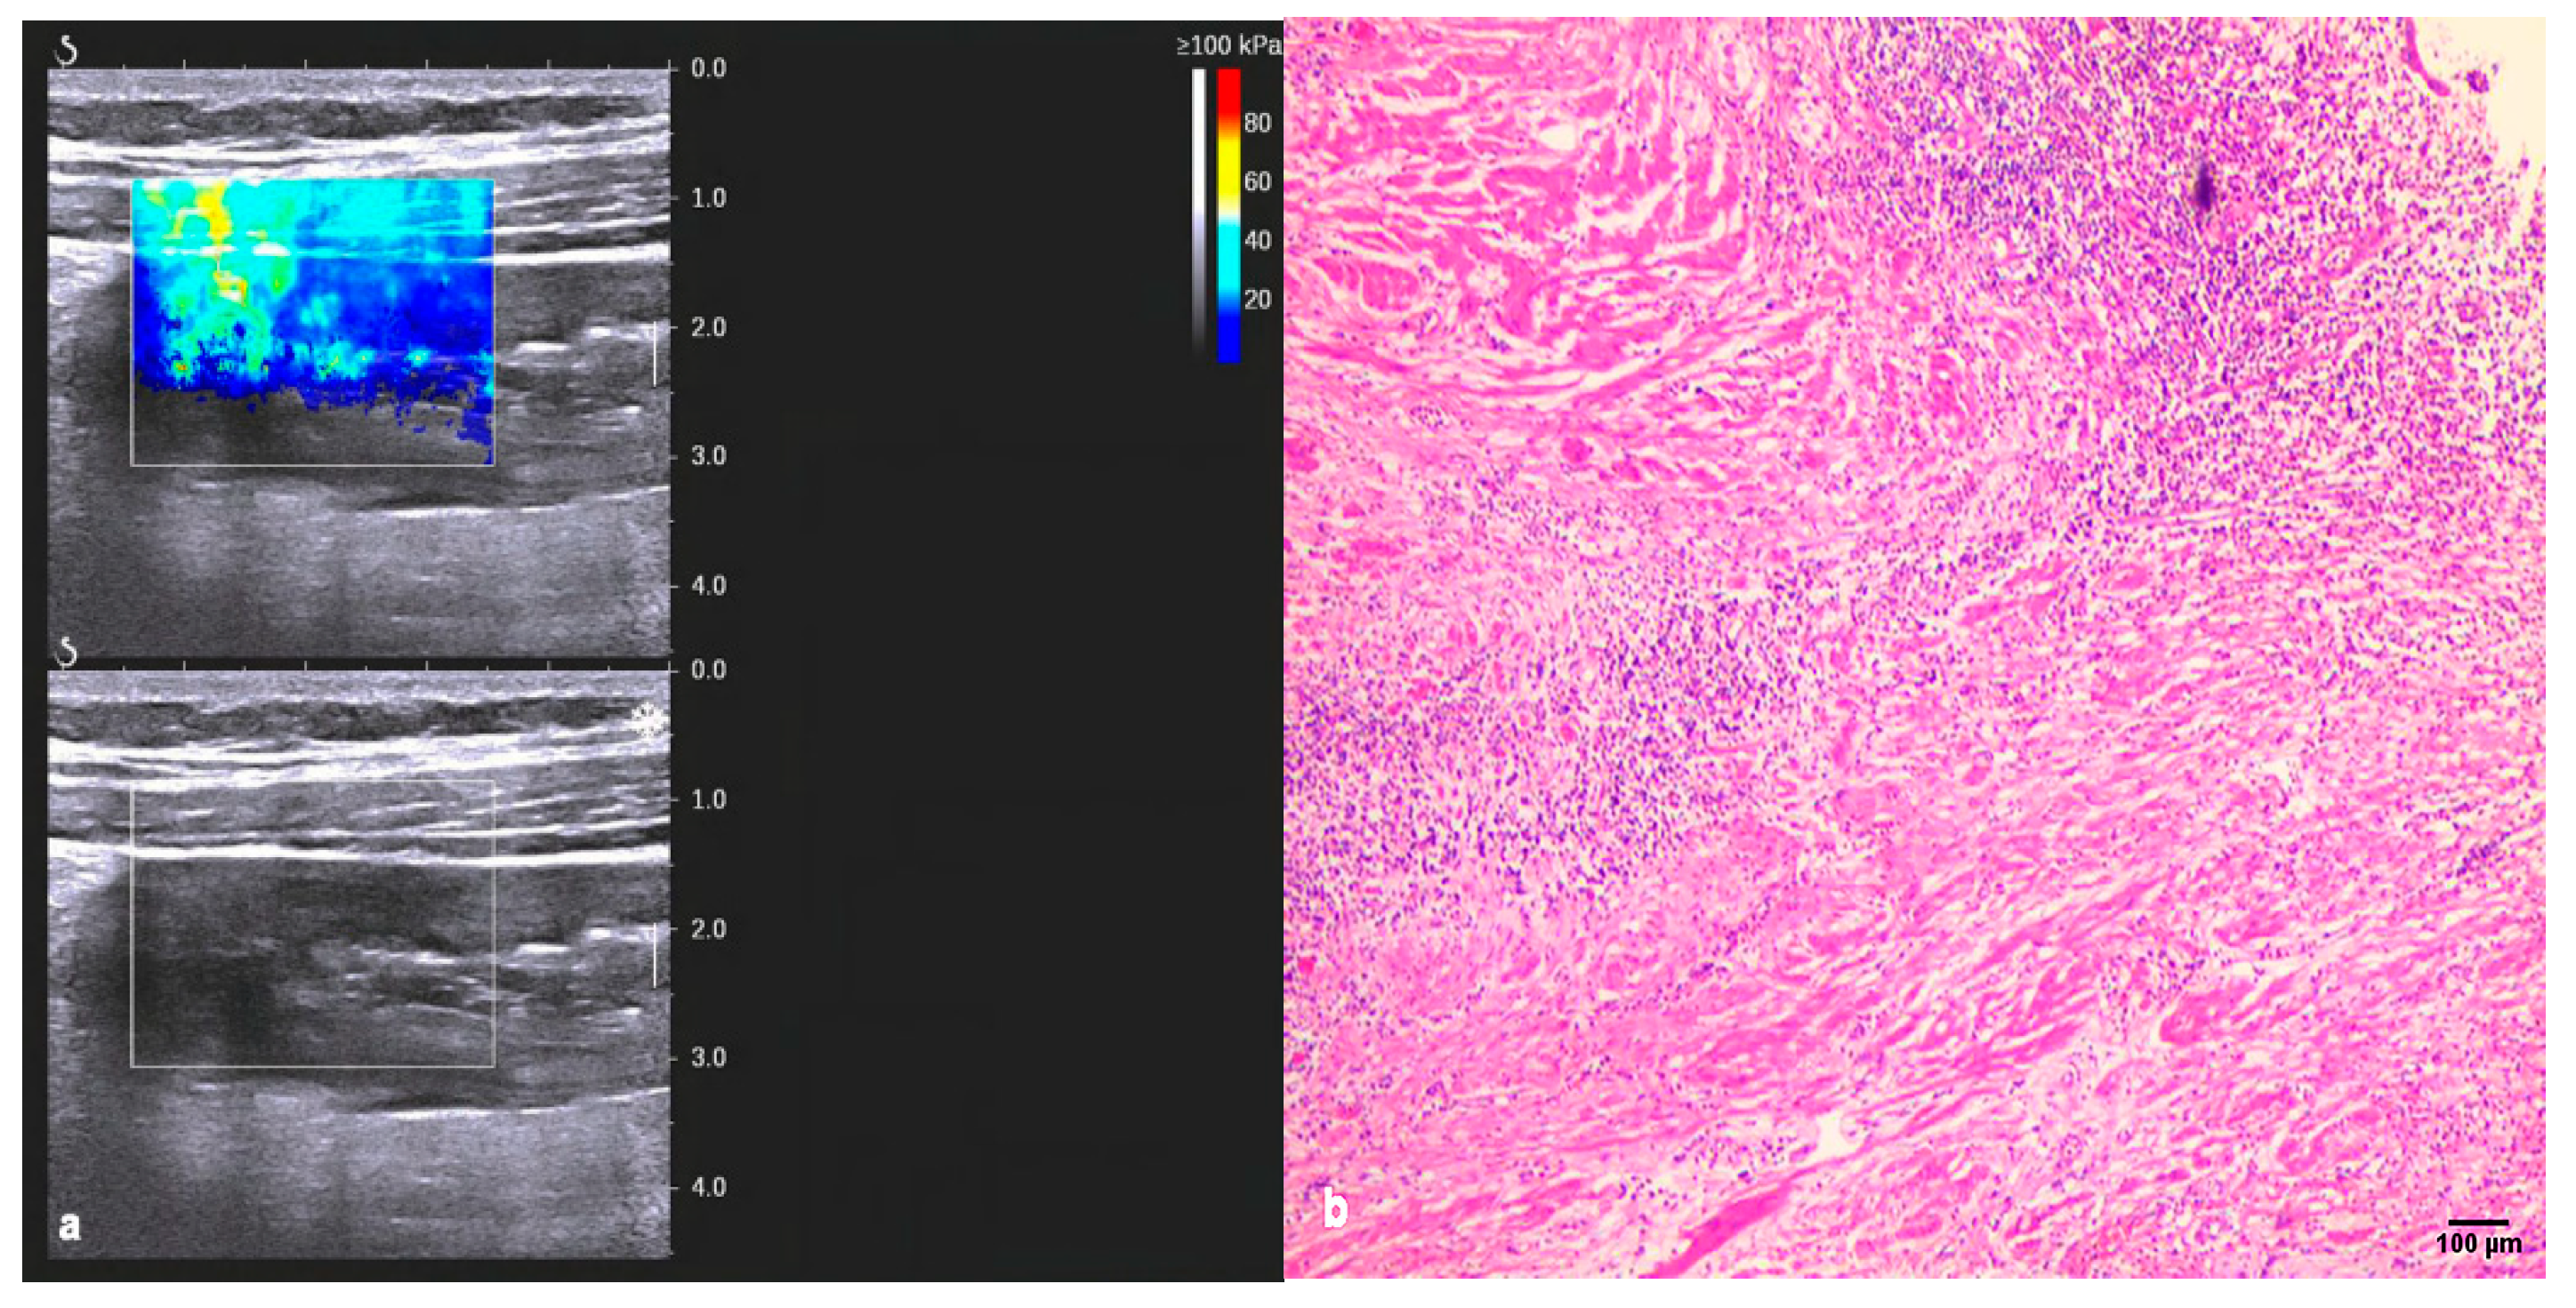

3.1. Conventional Ultrasound and Two-Dimensional Shear-Wave Elastography (2D-SWE)

| Inflammation | Fibrosis | p-Value | |

|---|---|---|---|

| Bowel wall thickness (mm) | 9.07 ± 4.14 | 10.53 ± 3.66 | NS |

| Limberg grading, n (%) | NS | ||

| I | 0 (0.00) | 1 (5.56) | |

| Ⅱ | 2 (10.53) | 8 (44.44) | |

| Ⅲ | 12 (63.16) | 7 (38.89) | |

| Ⅳ | 5 (26.32) | 2 (11.11) | |

| 2D-SWE, Emean, Kpa | 17.59 ± 7.21 | 35.24 ± 13.31 | 0.000 * |